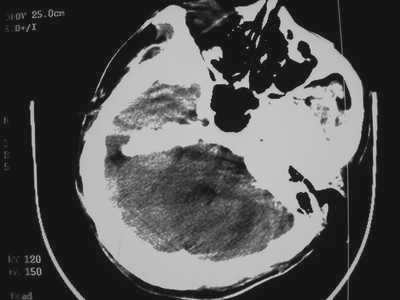

以下是引用卜一在2007-1-19 15:29:00的发言:[br]治疗前:1月14日右侧额叶皮质下低密度影,而治疗后:1月18日右侧阴影消失,新近出现左侧额叶侧脑室前角旁大片状低密度影,边缘模糊。支持—双侧额叶后部缺血性脑梗塞。